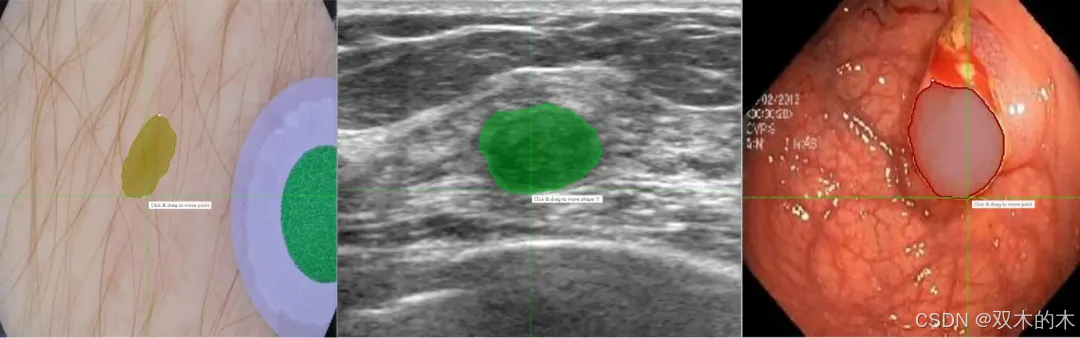

SAM-Med2D

更进一步地,针对医学图像场景,X-AnyLabeling 中同样提供了多种基于 SAM 微调的高精度模型,包括:

-

• SAM-Med2D[41]:通用医疗图像分割一切模型;

-

• LVM-Med SAM[42]:

-

• ISIC: 皮肤病灶分割一切模型;

-

• BUID SAM:超声乳腺癌分割一切模型;

-

• Kvasir SAM:结直肠息肉分割一切模型;

-

LVM-Med